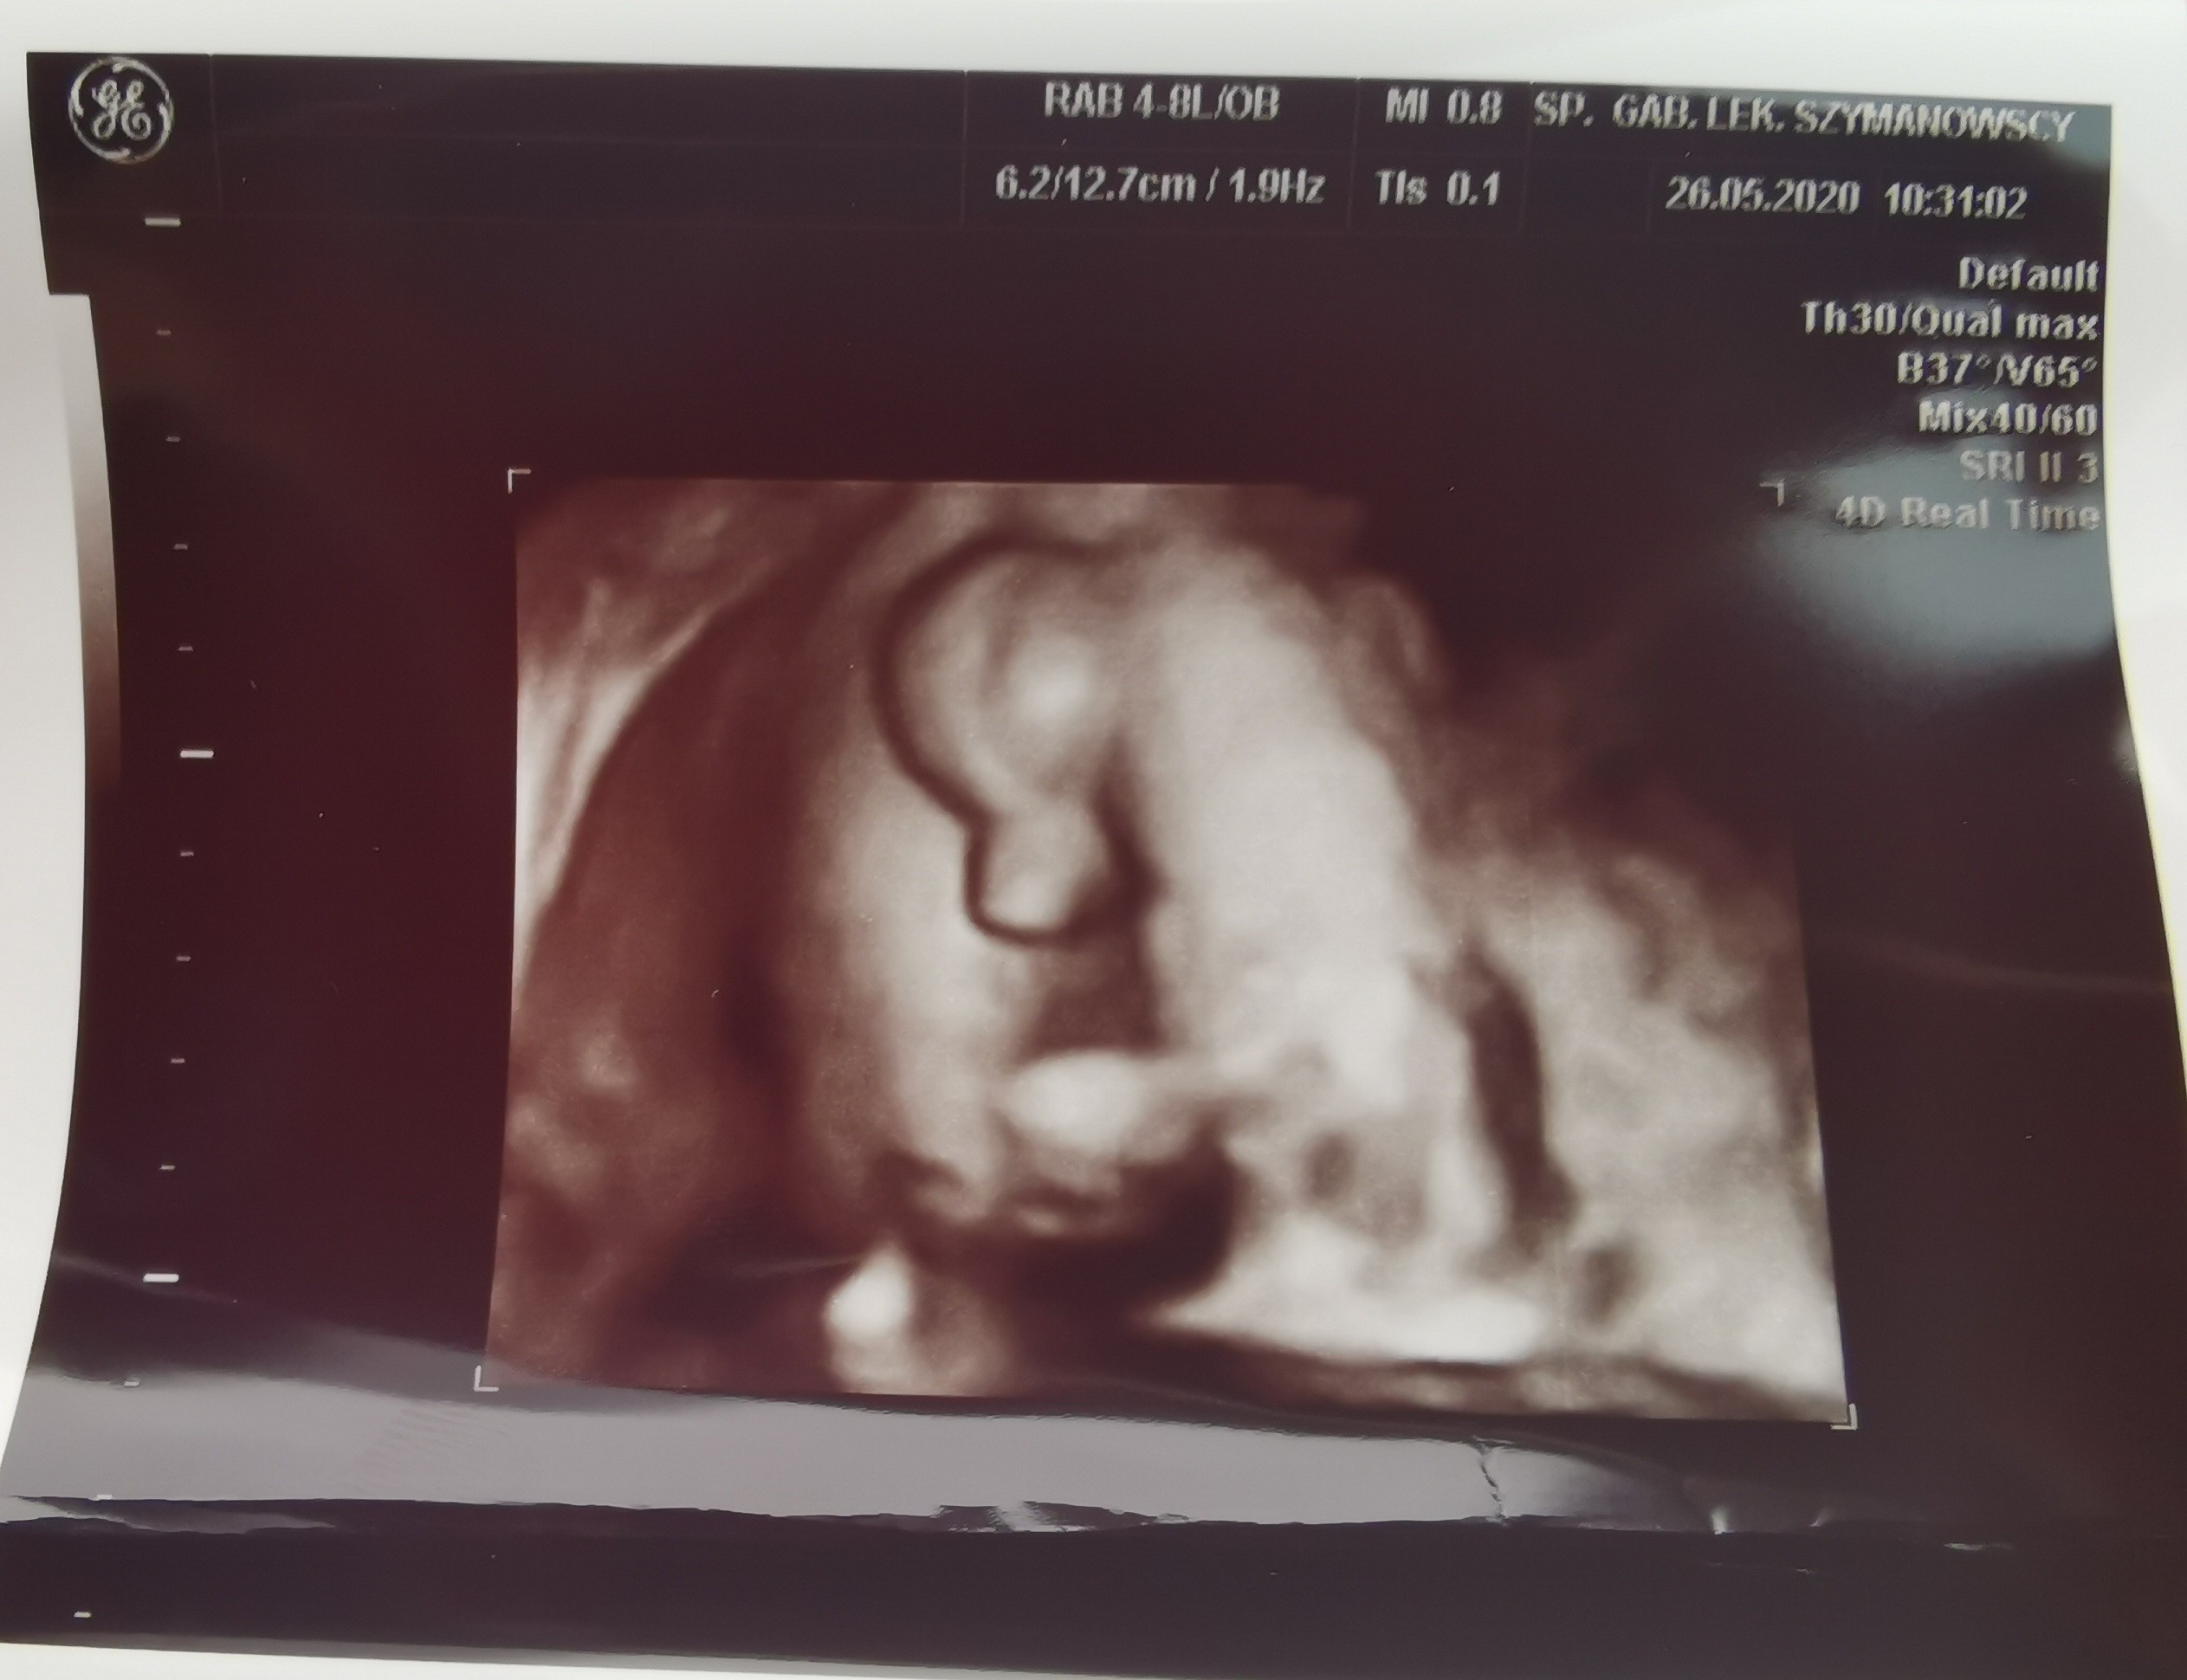

Masz świetne zdjęcia. Na prawdę bardoz ładne!